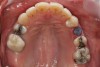

Figure 2a  Corticotomy SFOT. The patient presented with unesthetic anterior bridgework that was placed at age 14 to compensate for congenitally missing Nos. 7 and 10.

Figure 2a

Figure 2b  A corticotomy in SFOT is a surgical technique in which only the cortical bone is cut, perforated, or mechanically altered to the depth of the medullary bone and the medullary bone remains intact.

Figure 2b

Figure 2c  One week postsurgery with mesial buildups on Nos. 5 and 12 and thin pontics on archwire to conceal spaces during closure.

Figure 2c

Figure 2d  Prerestorative orthodontics was completed in 5 months. Final result 3 years, 4 months after completion.

Figure 2d

Figure 2e  Teeth Nos. 5 and 12 were converted to Nos. 6 and 11, and Nos. 6 and 11 were converted to Nos. 7 and 10. Nos. 4 and 13 were enlarged. Note stability and absence of orthodontic relapse. Before-and-after smiles.

Figure 2e

Figure 2f  Teeth Nos. 5 and 12 were converted to Nos. 6 and 11, and Nos. 6 and 11 were converted to Nos. 7 and 10. Nos. 4 and 13 were enlarged. Note stability and absence of orthodontic relapse. Before-and-after smiles.

Figure 2f

Figure 2g  Periodontist: Edward P. Allen, DDS, PhD. Prosthodontist: Robert R. Winter, DDS.

Figure 2g

Figure 2h  Periodontist: Edward P. Allen, DDS, PhD. Prosthodontist: Robert R. Winter, DDS.

Figure 2h